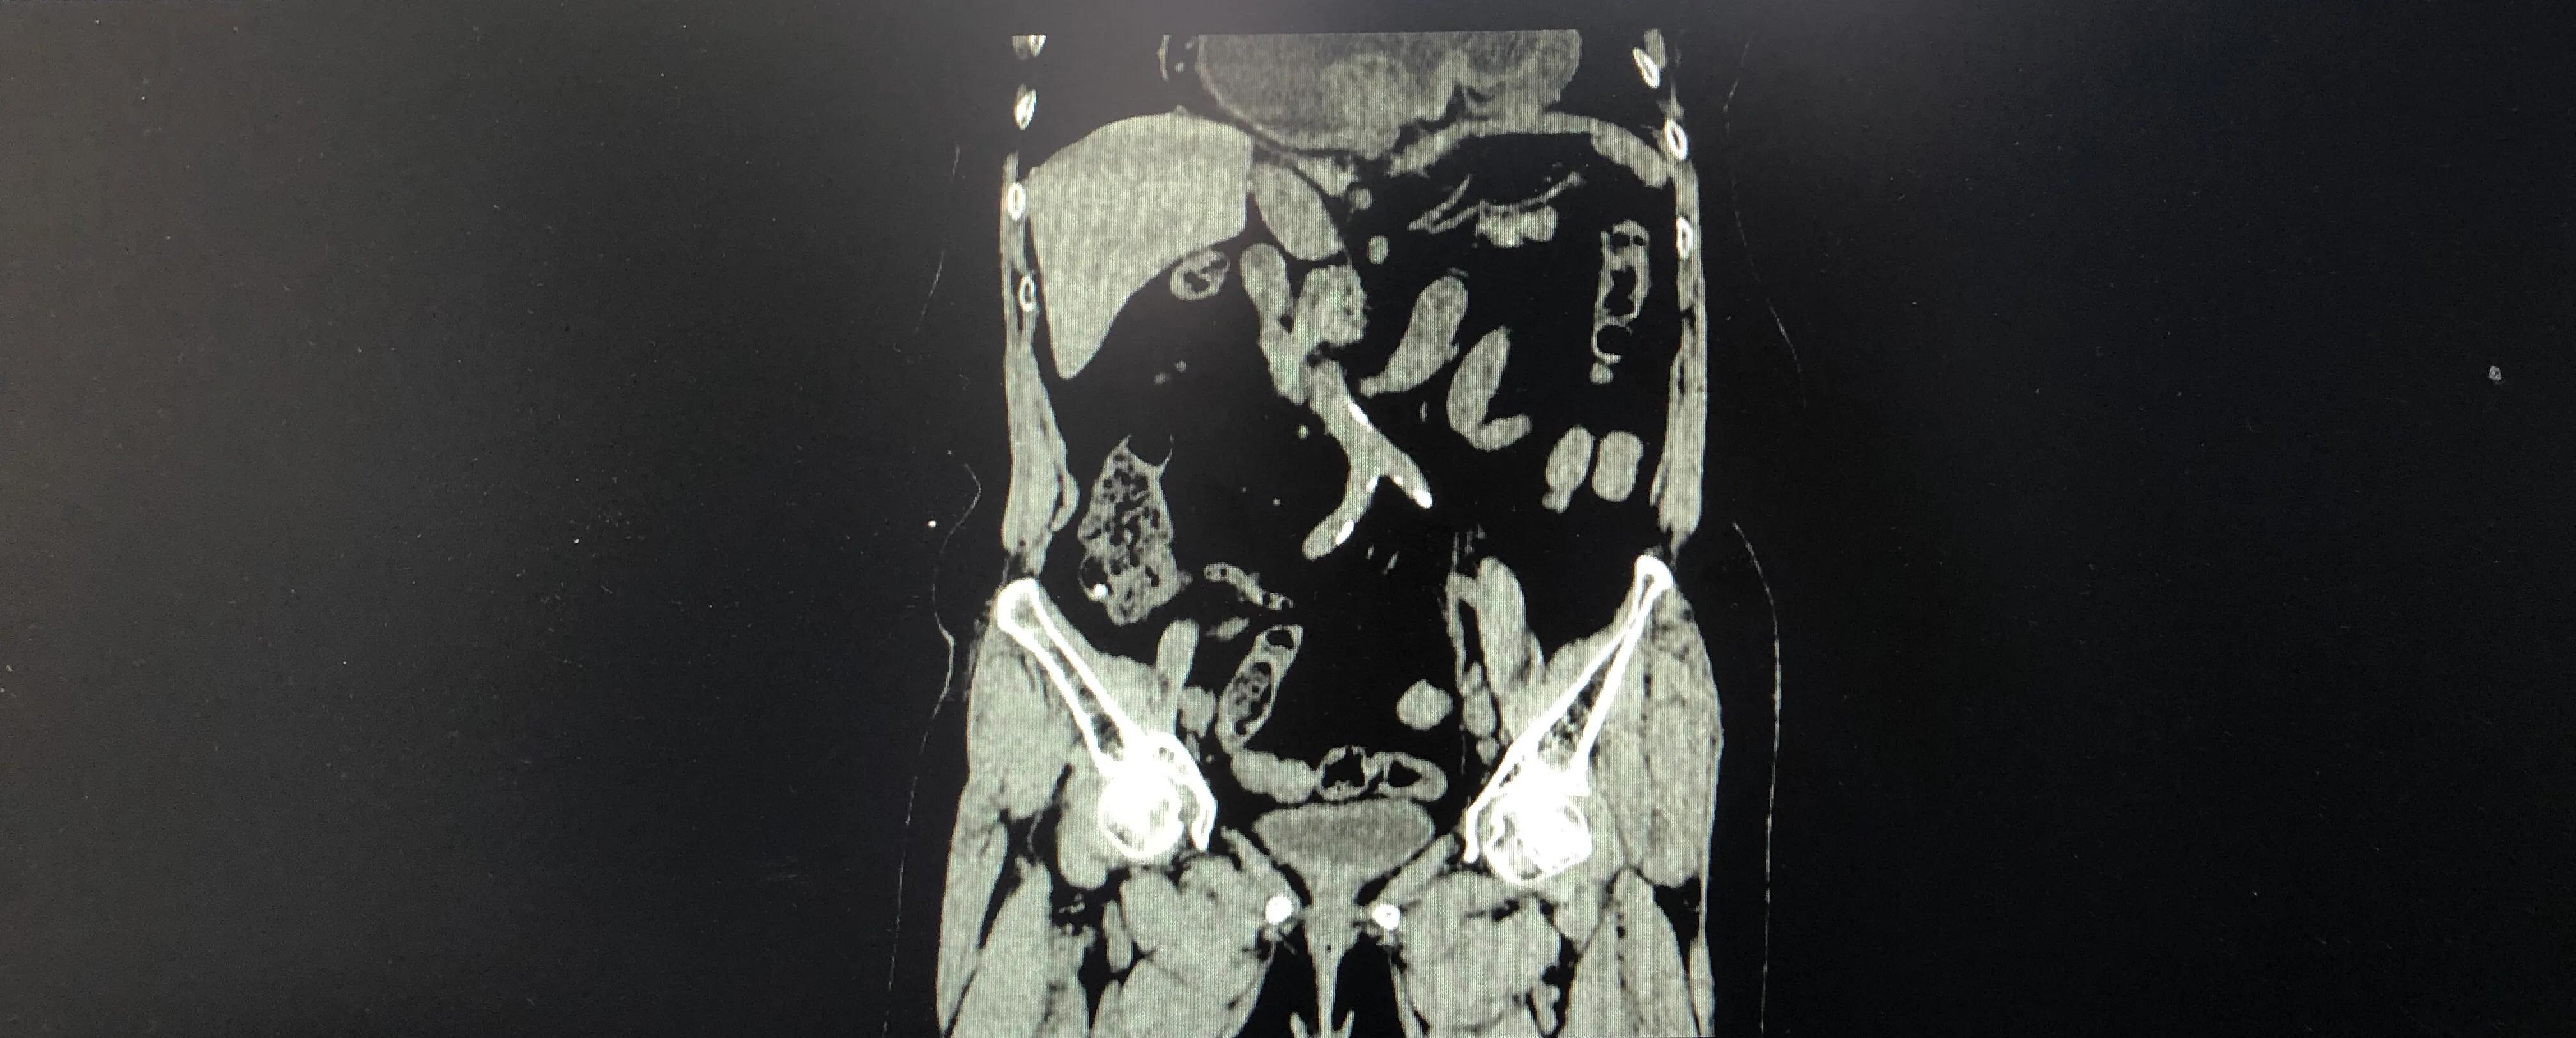

77岁的张女士喘憋不适逐渐加重,CT发现大部分的胃跑到胸腔去,压迫肺脏及心脏,如下图:

该病诊断食管裂孔疝。

巨大食管裂孔疝患者,贫血,胃扭转,出口梗阻,呕吐,无法正常进食,活动后就喘,胸疼,生活质量差,离不开人,你说这样的老人只能让人揪心,而且症状逐渐加重,贫血,营养不良相继出现,也会消耗着生命没有质量的生生活下去,令人痛心。这些症状是无解的,只有微创手术纠正他的异常解剖位置才会有好转。

巨大食管裂孔疝,超过1/3的胃,甚至全部胃+结肠等进入胸腔,到达如此程度的都是老年人,因为发展到这种地步需要时间,同时疝的年龄也大,需要10年20年的进展;高龄的老人一般都同时患有慢性病,心功能,肺功能状态不佳等。

巨大食管裂孔疝进入胸腔主要就是占了心脏和肺的地盘( 打个比方: 本来一人一个房间的胸腔,来了一个陌生的胖大胃挤他们的空间,心脏和肺脏被挤压受伤)也就是说,有一部分心肺症状其实是巨大食管裂孔疝引发的,只有做了手术才能缓解( 小提示: 这种情况下不做手术是无解的噢)。